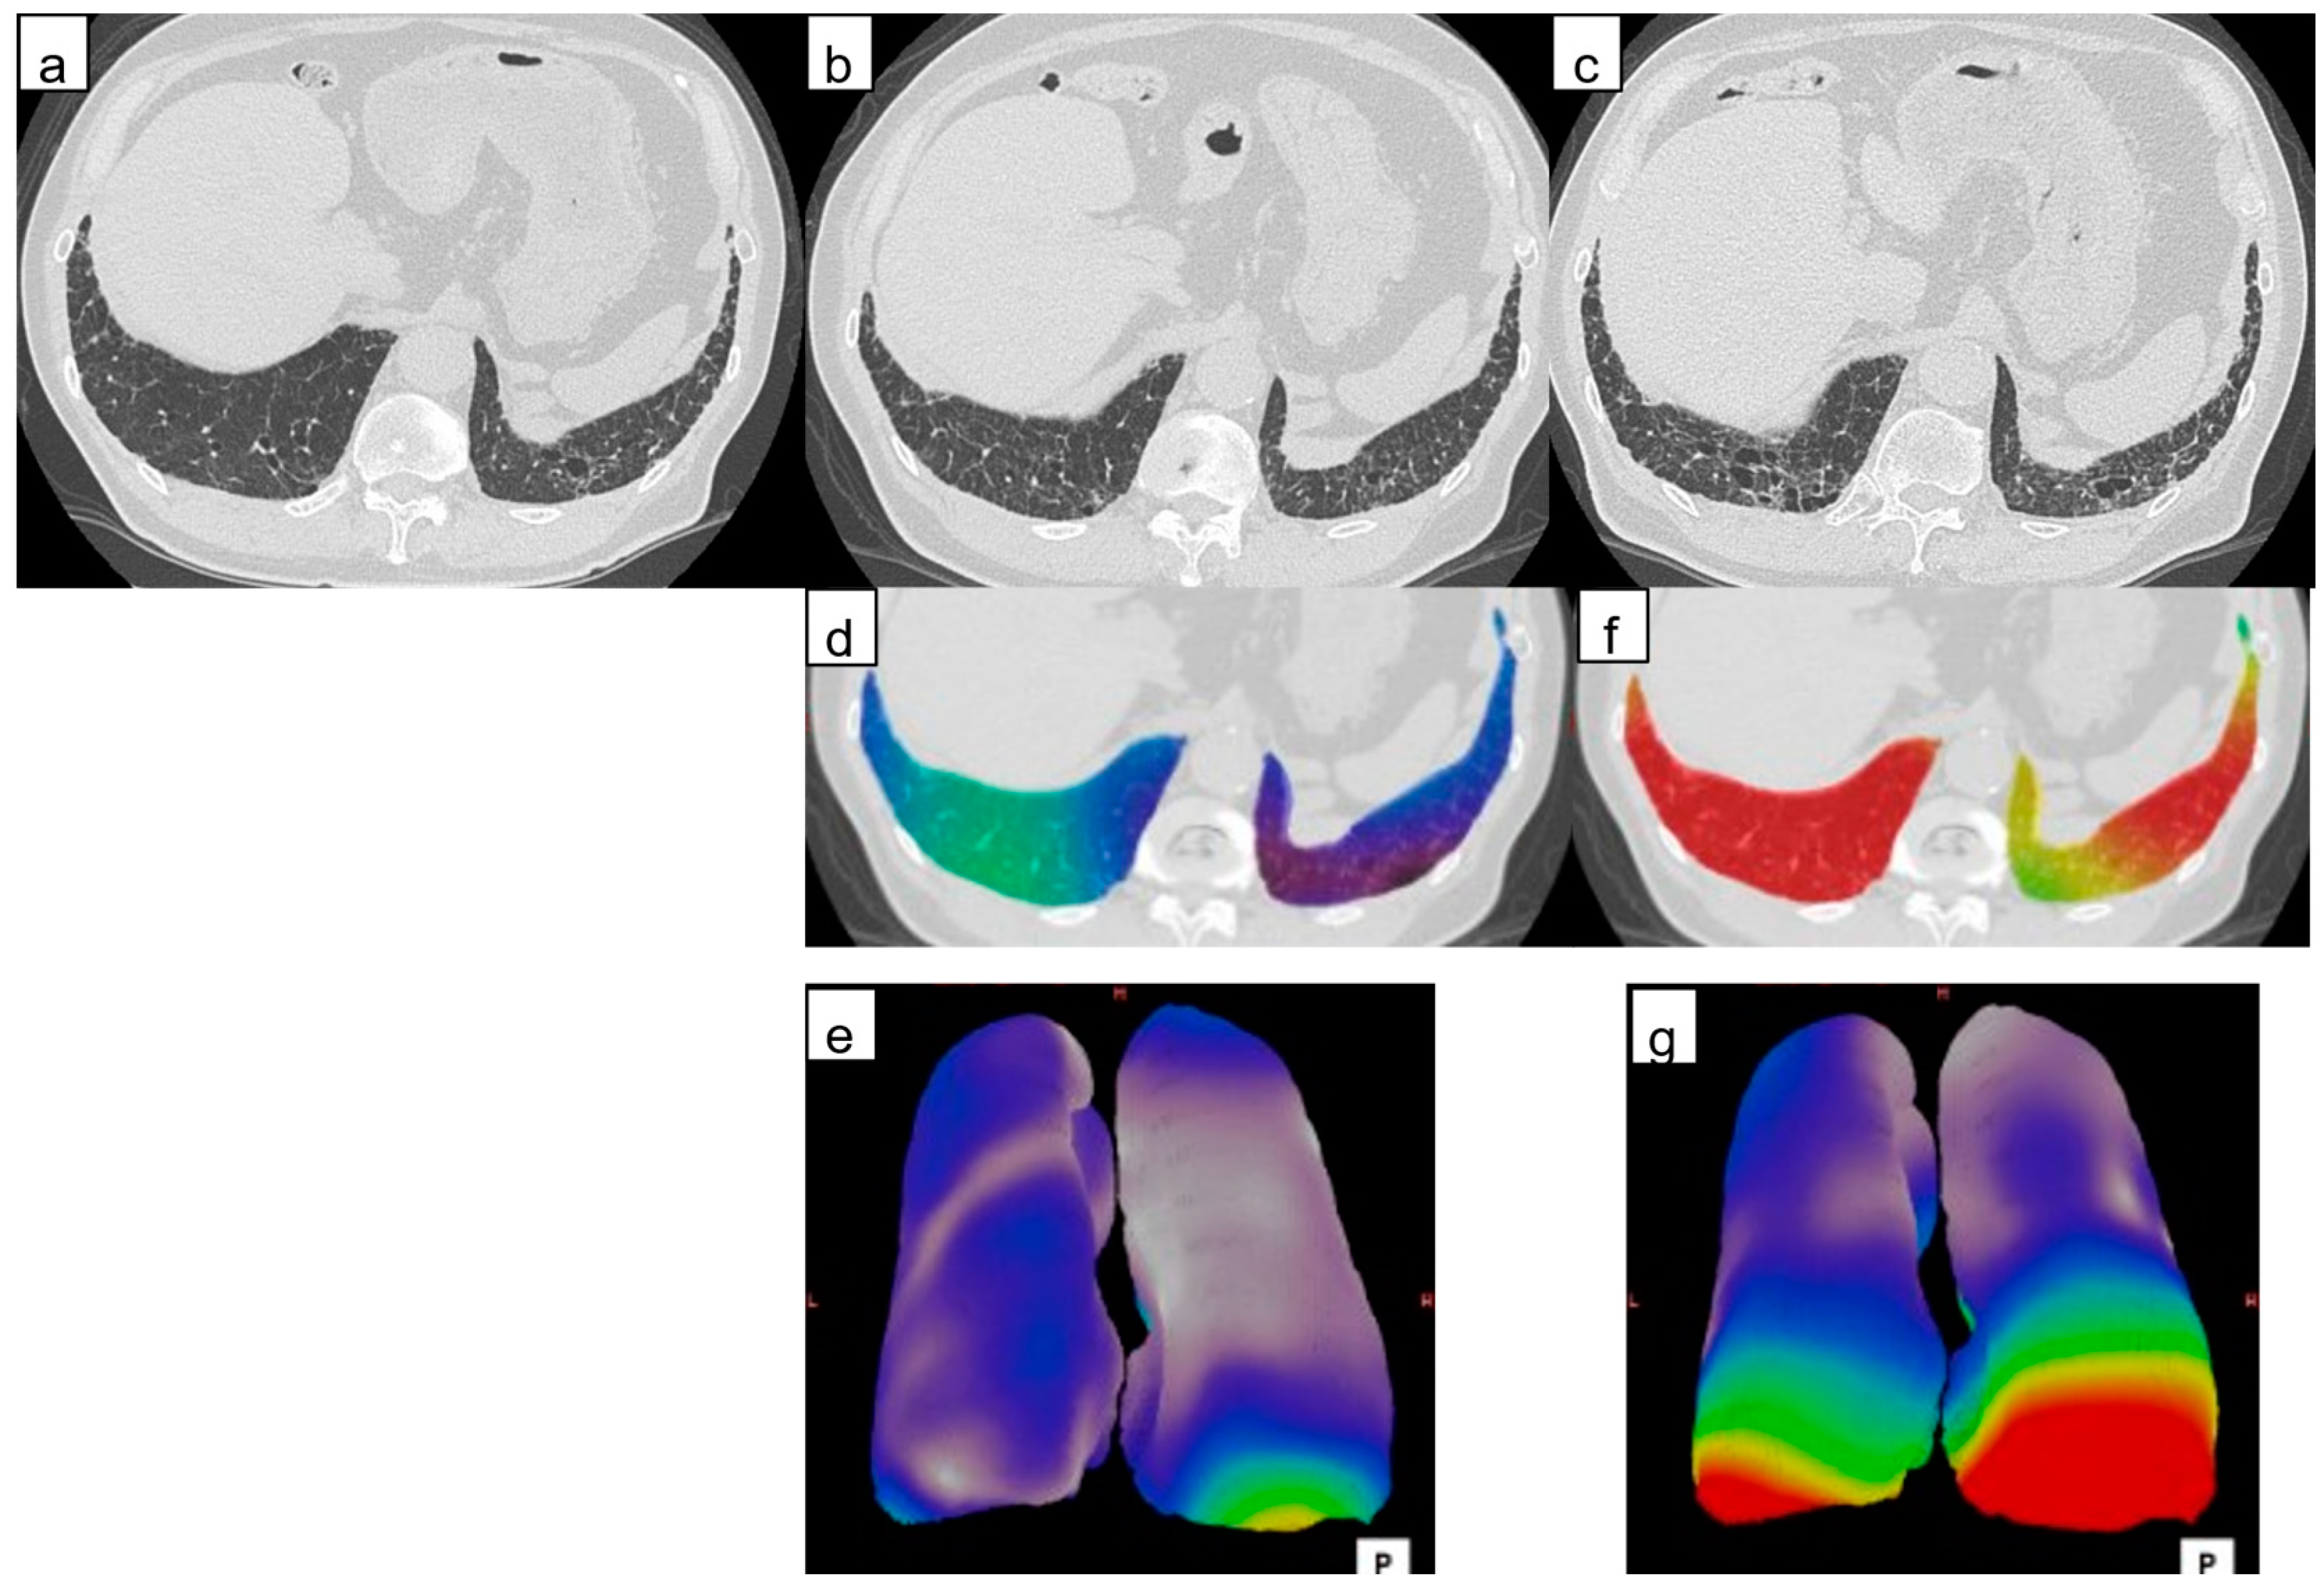

2.3.1. Architectural Distortion Measurement by 3D-AD